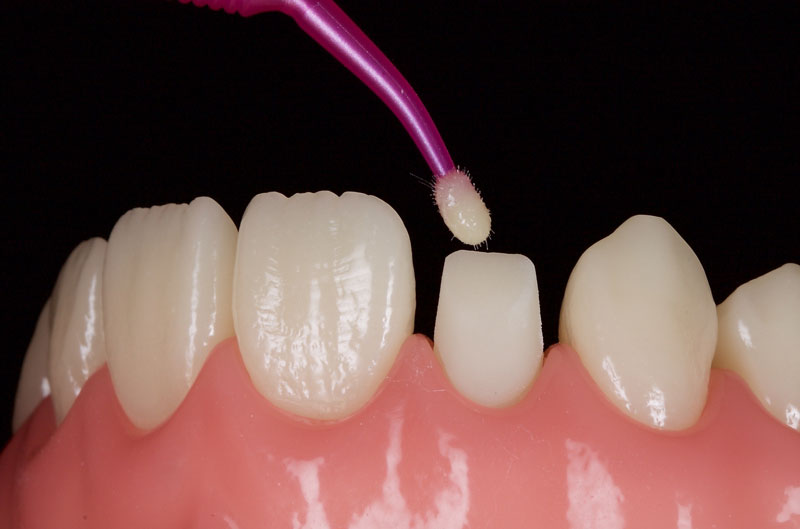

The tooth is then etched, primed, and bonded with a dentin-bonding agent. I prefer a 4th-generation dentin bonding agent since it has the best data and highest bond strengths (Fig. 7).